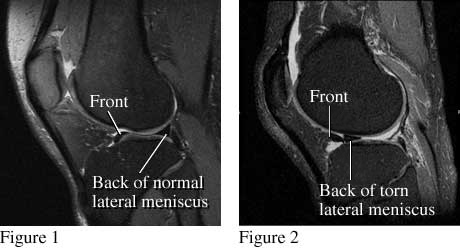

MRI images of torn meniscus

Figure 1 is a side view of the knee that shows the normal location of the outside, or lateral, meniscus. Figure 2 is a similar view that shows a piece of meniscus that has been torn and moved.